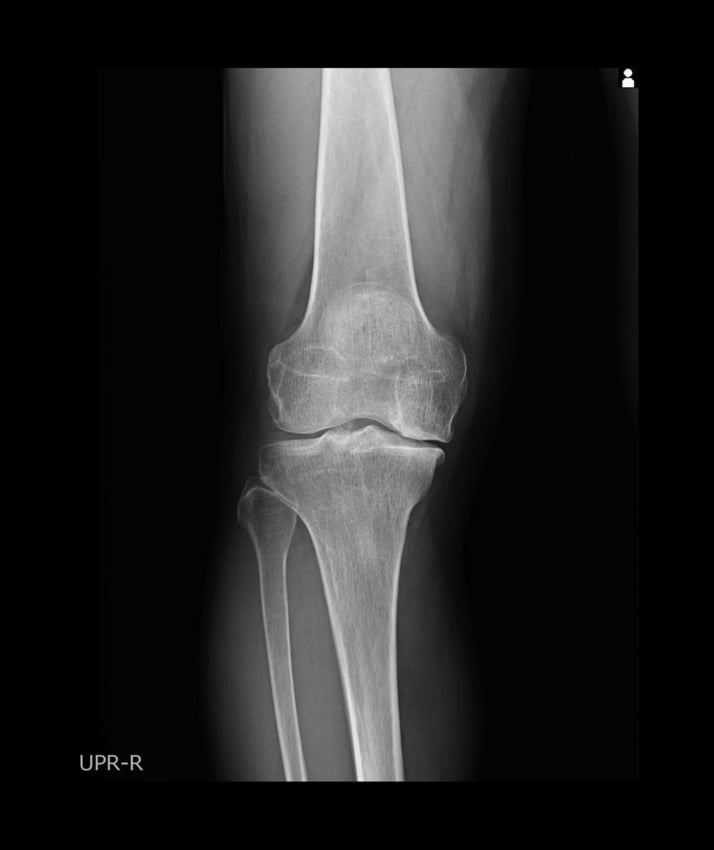

変形性膝関節症の患者のレントゲン写真